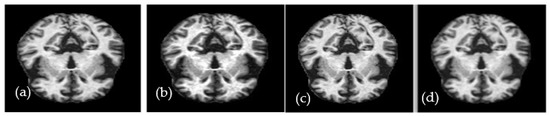

Figure 2.

A visual example of the proposed preprocessing step to enhance the contrast of MRI images, where figure (a,c) are the original and (b,d) are with noise removed and enhanced.

where I(x, y) represents the value of each pixel in the image, the parameter represents its minimum value, the parameter represents the highest value, and represents the enhanced pixel because of applying image contrast. A high-contrast example of an axial MRI brain image is shown in Figure 2. The median filter is a method for reducing noise without introducing edge blur. It is highly suitable for improving the necessary MRI pictures. By comparing each pixel in the image to its surrounding pixels, the median filter can determine which pixels are noise. Each pixel value in the image is passed through the filter (also known as a kernel) and changed to the matching median value. Sorting the values of the pixels in the area yields the median value, which is then used to replace the offending pixel with its matching middle value. Figure 2 depicts the outcome of applying the median filter with a size of (3 × 3) to a sample image.